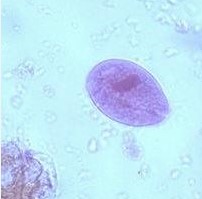

20

New cards

term image

entamobea histolityca cysta